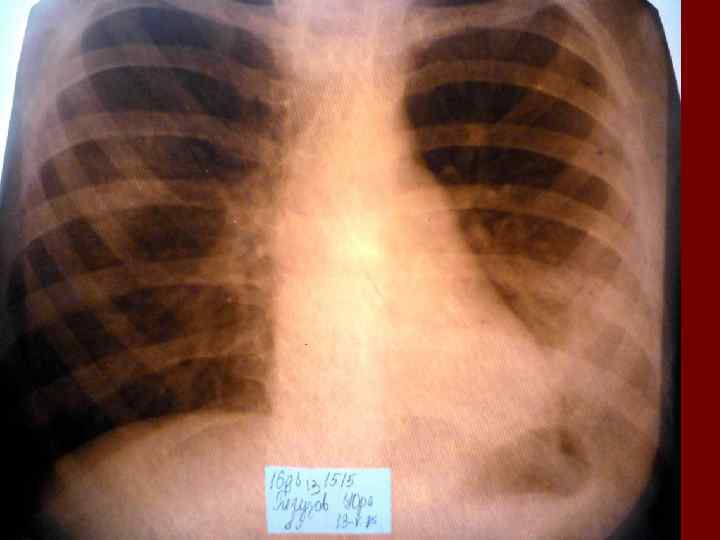

Пневмония Воспалительный процесс в респираторных отделах легкого с наличием внутриальвеолярной экссудации. n Это острое инфекционное заболевание легочной паренхимы, диагностируемое по синдрому дыхательных расстройств и/или физикальным данным при наличии очаговых или инфильтративных изменений на рентгенограмме. n Пневмония – это, прежде всего, клинический диагноз, который ставит врач у постели больного, и только затем подтверждает рентгенологически. n

Пневмония - это неспецифическое воспаление легочной ткани, в основе которого лежат инфекционный токсикоз, дыхательная недостаточность, водно – электролитные и прочие метаболические нарушение с патологическими изменениями во всех органах и системах детского организма. Заболевание диагностируется на основании синдрома дыхательных расстройств и/или физикальных данных и верифицируется рентгенологически выявлением инфильтративных изменений в легких.

Долевая пневмония характеризуется лобарным пневмоническим инфильтратом. Крупозная ( пневмококковая) пневмония диагностируется прежде всего по клиническим данным. Крупозная пневмония сохраняет свою типичную картину пневмококковой пневмонии: острое начало с характерными клиническими данными, циклическое течение, несклонность к деструкции, гомогенной и лобарной инфильтративной тенью при рентгенологическом исследовании. Вместе с тем, широкое использование антибиотиков способствовало значительному снижению числа крупозных пневмоний у детей. Интерстициальная – редкая форма пневмоний, при которой оказывается поражен прежде всего интерстиций. Как правило, интерстициальная пневмония обусловлена вирусами, пневмоцистами, внутриклеточными микроорганизмами и грибами.

Морфологическую форму пневмонии определяют по клинико – рентгенологическим данным: выделяют очаговую, очагово – сливную, долевую ( крупозную), сегментарную и интерстициальную пневмонии. Очаговая – наиболее распространенная форма. Пневмонические очаги чаще бывают размером 1 см и более. Очагово – сливная – инфильтративные изменения в нескольких сегментах или во всей доле легкого, на фоне которых могут быть видны более плотные участки инфильтрации и/или полости деструкции. Сегментарная – в процесс вовлекается весь сегмент, который, как правило, находится в состоянии гиповентиляции, ателектаза. Морфологическая картина воспаления при очаговых и сегментарных пневмониях связана с первичным инфекционным воспалением в бронхах, что дает основание отнести эти варианты поражения легочной ткани к бронхопневмониям, нередко сопровождающихся бронхообструктивным или бронхообтурационным синдромами. В настоящее время данный тип пневмоний у детей встречается наиболее часто.